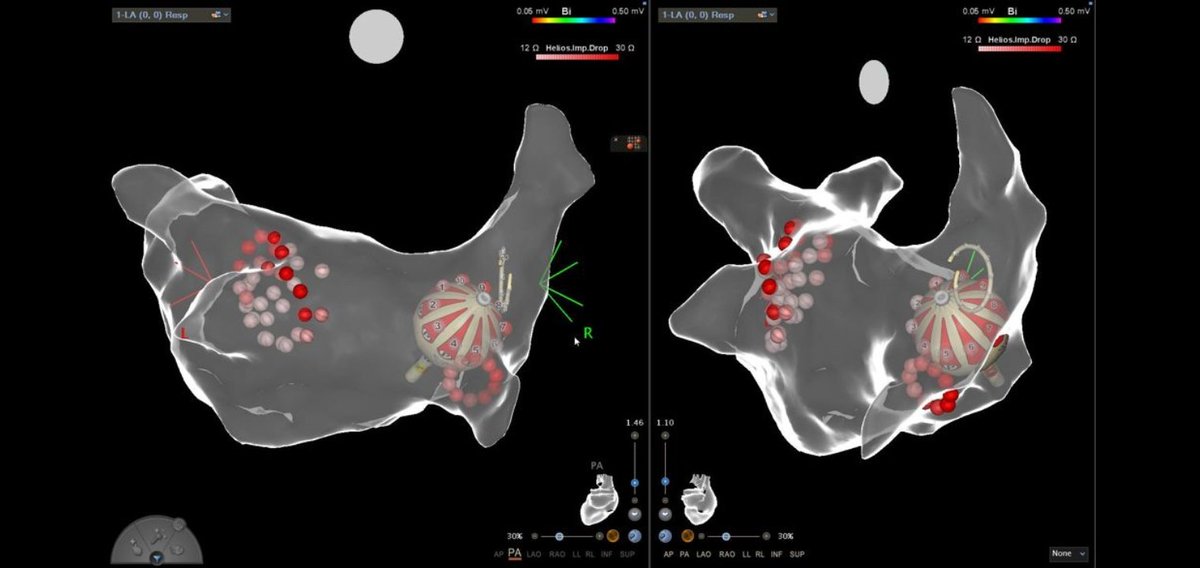

Jason Garcia retweetledi

Single shot PVI in under 6 seconds 😳

Heliostar looking promising after initial 10 cases at @BartsHospital! Minimal fluro, ablation and lab time.

Keep up the good work @mcfinlay & @Prof_Schilling!

🔥 or 🧊 #EPeeps ?

@RachaelRobsonEP @JVGEP @BiosenseWebster